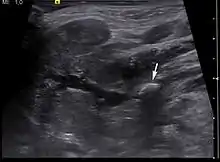

Diagnosis is usually made by characteristic history and physical examination. Diagnosis can be confirmed by x-ray (80% of salivary gland calculi are visible on x-ray), by sialogram, or by ultrasound.

- ↑ "UOTW #70 - Ultrasound of the Week". Ultrasound of the Week. 24 April 2016. Retrieved 27 May 2017.